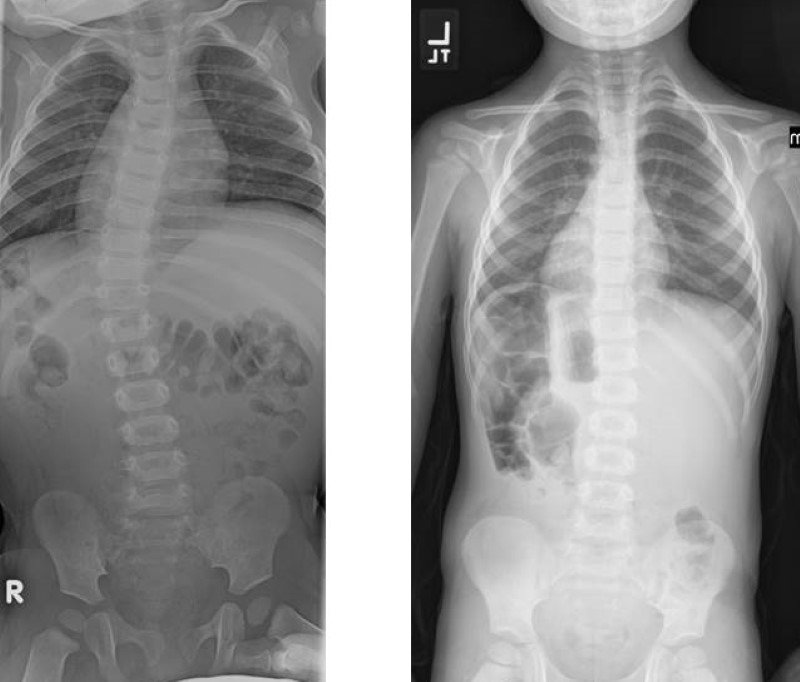

Omurgaya arkadan bakıldığında eğrilik düz durulduğunda bile fark edilebildiği gibi bazen bu denli net değildir ve ancak öne eğilme durumunda, kontroller ve röntgen filmlerinde anlaşılabilir. Skolyoz genelde ergenliğin başında,çeşitli nedenlerle ortaya çıkmaktadır.